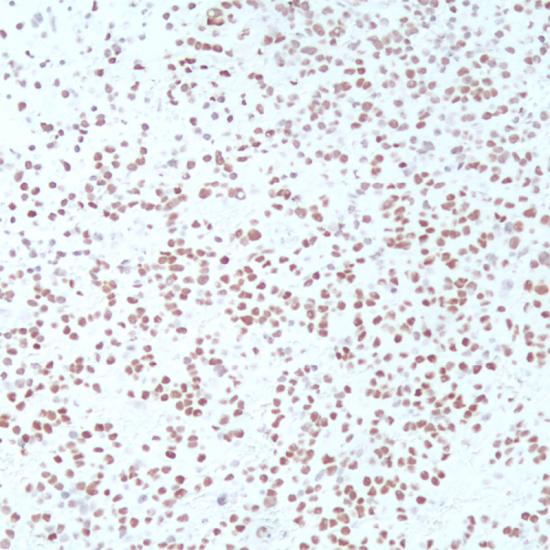

PIT-1

生長激素因子-1(PIT-1)抗體試劑(免疫組織化學(xué)法) 閩廈械備20190145號

細(xì)胞核

垂體腺瘤

PIT-1也稱為生長激素因子-1(GHF-1),是POU蛋白家族的成員,對于垂體前葉的發(fā)育及GH,PRL,TSH的合成具有極為重要的作用。該抗體主要用于垂體瘤的研究。